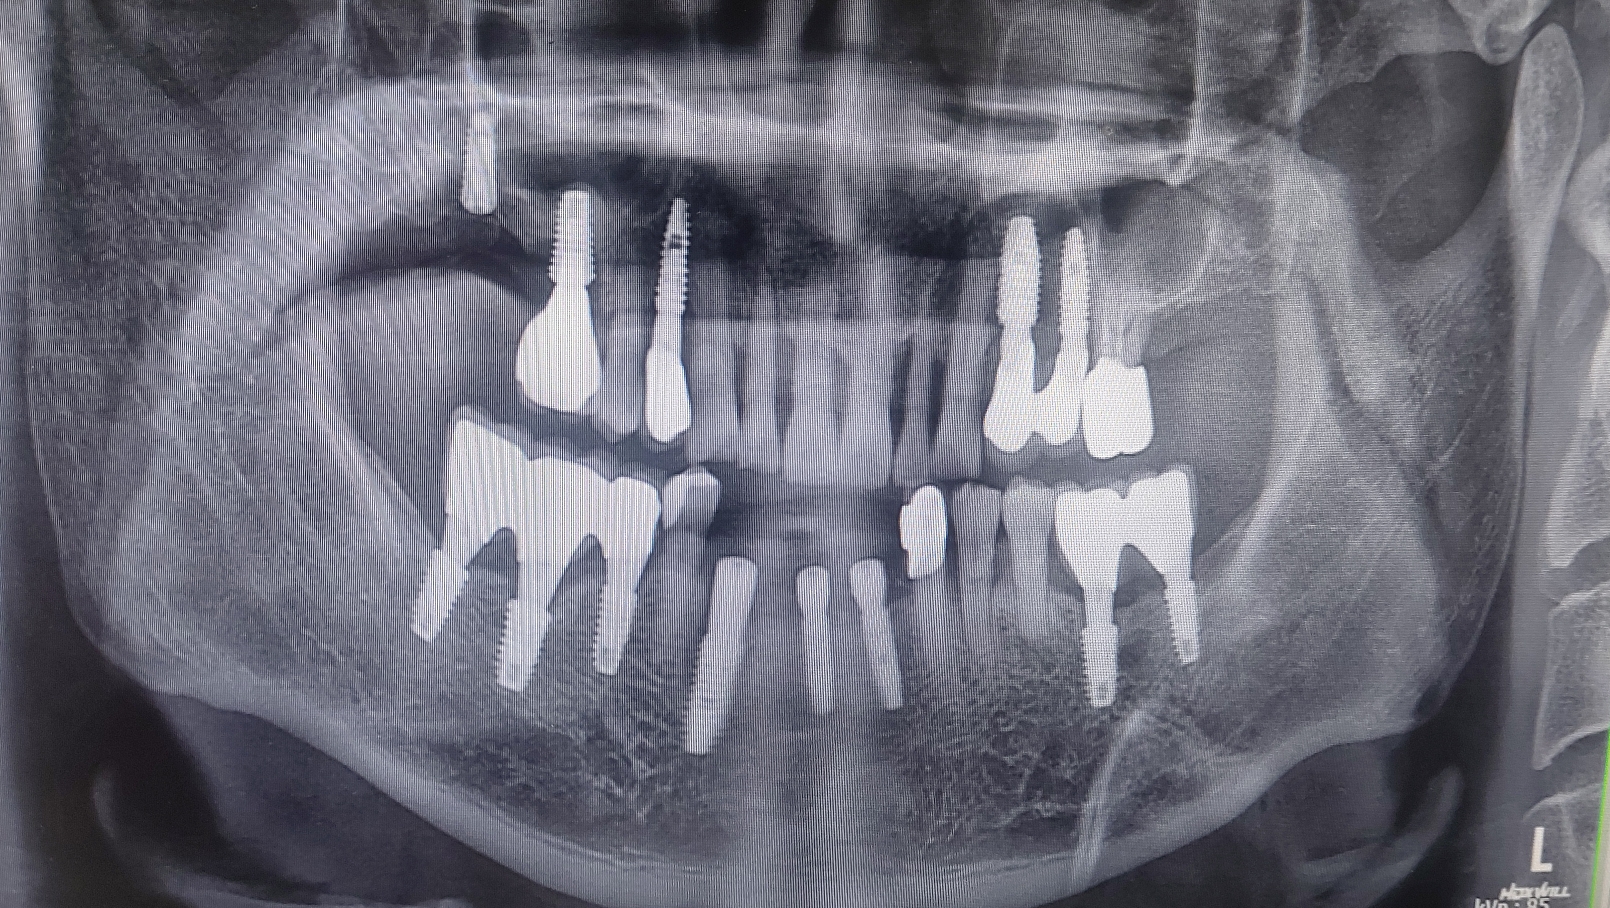

수면마취후 수술을 권해 드렸고 즉시 부하로 최대한 빨리 5일정도면 예쁜 고정성 임시치아가 가능하다고 말씀드렸습니다.

지난 금요일 오후에 수술을 시행하고 다음 수요일에 치아를 넣어 드렸습니다. 임시 치아라 밝은 느낌은 있었지만 추후 수정 가능하다고 말씀드렸습니다. 치아가 자연스럽게 잘 나와서 서로 기분이 좋았던 증례입니다.

환자분 오랬동안 아래 송곳니 쪽이 붓고 불편했지만 끝까지 치료를 미루어 오시다가 수면마취와 즉시 부하로 잘 고민이 해결되었습니다.